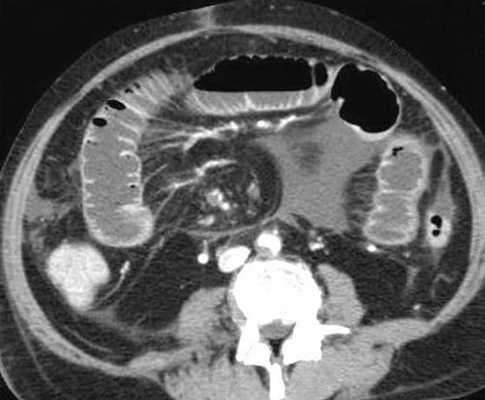

Для странгуляции тонкой кишки характерны утолщение стенок кишечника, васкулярные нарушения и выраженные патологические изменения в брыжейке и в брюшной полости. Диагностические находки включают в себя:

-утолщение стенки кишки циркулярного типа. Важно помнить, такой тип утолщения стенок тонкой кишки при непроходимости как правило связан с сосудистыми нарушениями;

-нарушение нормального контрастного усиления стенок кишки. Изменения варьируют от гиперконтрастирования до полного отсуствия контрастного усиления. Различные варианты этих изменений между описанными выше крайностями могут наблюдаться одновременно в разных сегментах тонкой кишки. Полное отсутствие усиления означает артериальный рефлекторный спазм и свидетельствует в пользу тяжести поражения;

-появление патологических плотностей в брыжейке в виде распространяющихся матовых инфильтратов и тяжистости за счет кровоизлияний в жировые ткани;

-при заворотах нарушается нормальная сосудистая анатомия брыжейки. Сосуды как бы закручиваются вокруг оси заворота и тянут за собой измененный брыжеечный жир- по типу раковины улитки или торнадо. Для большей наглядности представьте себе кусок расправленной ткани на столе, которую вы прижали пальцем и начали закручивать не отрывая ваш палец от стола. На КТ сканах часто можно увидеть характерный признак конусовидной спирали (whirl sign);

примеры странгуляционной осложнённой непроходимости с характерными изменениями в брыжейке, внутрибрюшинном жире, утолщением стенок тонкой кишки и нарушением контрастного усиления.